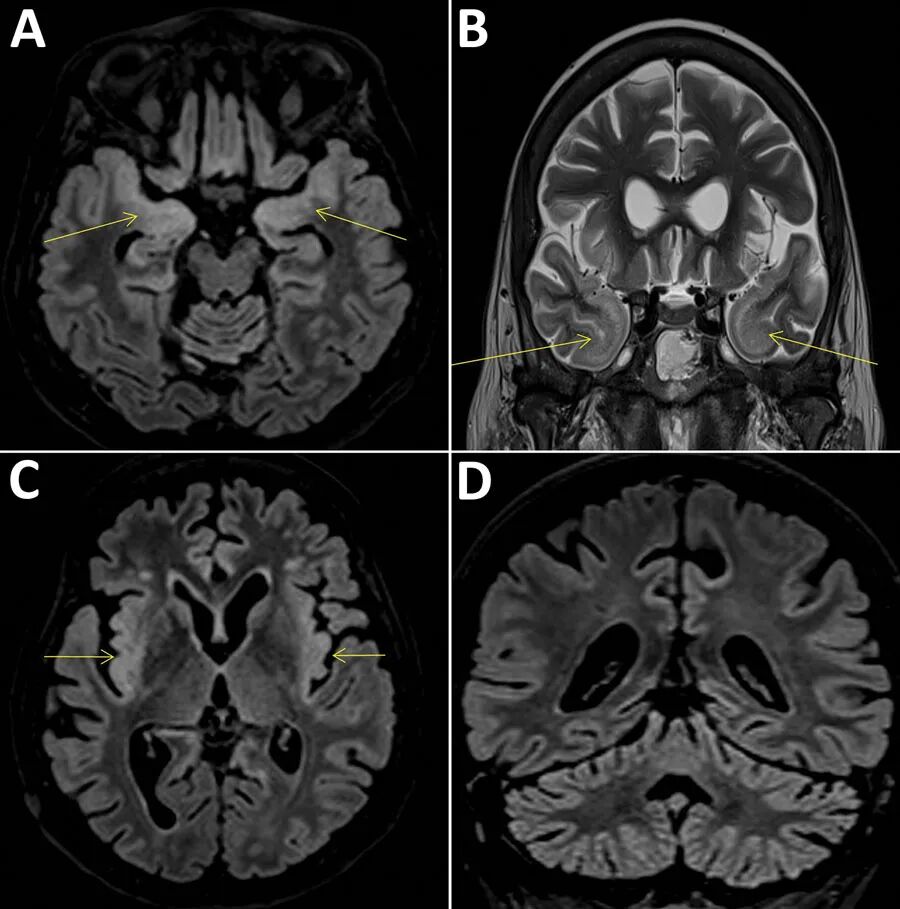

入院之后,医生不仅为她做了微生物检测,还做了脑活检,但却找不到任何能够导致脑炎发作的原因。6个月后,这位妇人最终因为严重的脑炎去世,只给医院里的医生留下了一地的谜团。在这位病患死后,Pitié-Salpêtrière的医生将妇人的脑组织送到了对传染病更有研究的Henri Mondor医院,希望他们能够找出答案。

通过Rodriguez医生的测序方法,医院内的研究团队马上从妇人的活检体中提取出了核酸,进行了基因测序。没想到,在这次测序之后,医生们竟然在妇人的脑内发现了一种神秘的病毒。这种病毒毒性极强,妇人的脑炎很可能就是因它引发的。而在将病毒的序列和其他已经发现的病毒比较之后,医生们基本确认,这是一种全新的病毒。